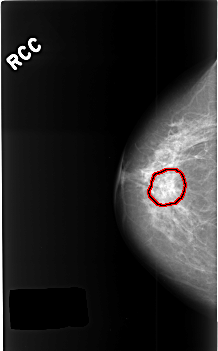

C_0398_1.RIGHT_CC

RIGHT_CC LINES 4552 PIXELS_PER_LINE 2832 BITS_PER_PIXEL 12 RESOLUTION 50 OVERLAY

FILE: C_0398_1.RIGHT_CC.OVERLAY

TOTAL_ABNORMALITIES 1

ABNORMALITY 1

LESION_TYPE CALCIFICATION TYPE AMORPHOUS DISTRIBUTION CLUSTERED

ASSESSMENT 4

SUBTLETY 3

PATHOLOGY BENIGN

TOTAL_OUTLINES 1

BOUNDARY